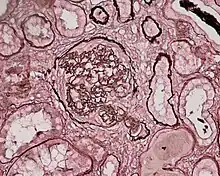

Photomicrograph of a kidney biopsy from a person with crescentic glomerulonephritis showing prominent fibrocellular crescent formation and moderate mesangial proliferation in a glomerulus. Hematoxylin and eosin stain.